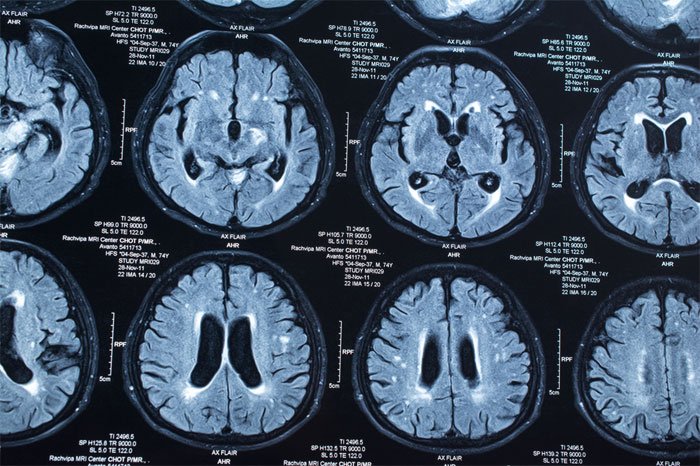

Мозг лежит в центре нашей личной вселенной. Он превращает хаотичный мир, состоящий из швыряющихся частиц, в восприятие смысла и стабильности. Помимо создания сенсорной репрезентации реальности, мозг позволяет нам осознавать себя и других. Каждый процесс нервной системы может быть деконструирован на ощущения, движения, эмоции, память и общение. Мозг позволяет человеку создавать, исследовать, взаимодействовать и стремиться к чему-то лучшему. Он содержит в себе наши величайшие мечты и надежды, а также наши страхи и кошмары. Это то, откуда берет начало жизнь и религия. Это место, где живут добро и зло. Это место, где жизнь заканчивается.

Центральная аксиома медицины проста. Поддержи и защити мозг в клинике неврологии Юсуповской больницы https://yusupovs.com/clinics/neurology/. Цикл TCA, белки G, анатомия сердца, баланс кислота/основание и почка, а также транспорт кислорода с кровью и легкими — все это критически важно для поддержания жизни мозга.

Остаётся многое, что нужно знать о мозге. Несмотря на то, что каждый год достигаются огромные успехи, изучение мозга остается в зачаточном состоянии. Этот черный ящик пугает многих студентов-медиков, но он также был источником очарования для величайших ученых, писателей и философов мира.